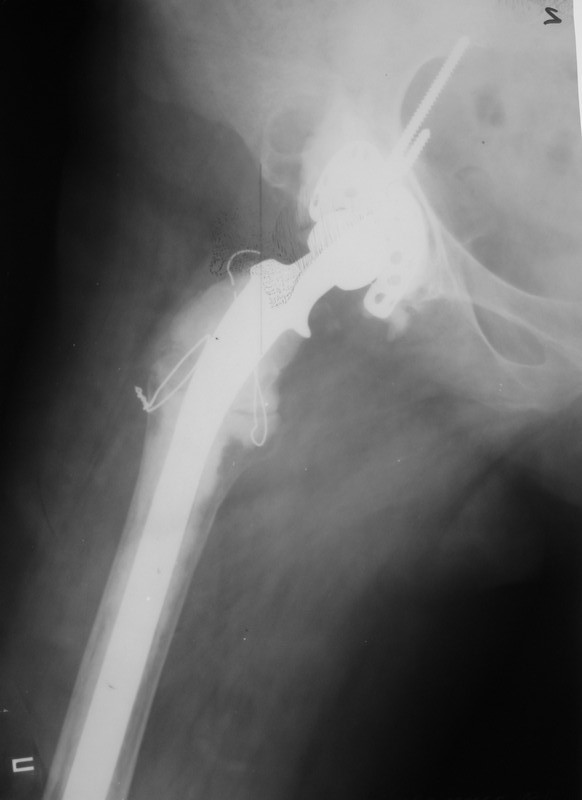

Уважаемые коллеги,в клинику поступила пациентка 51год с нестабильным антипротрузионным кольцом и вывихом эндопротеза. В течени длительного времени у пациентки ревматойдный полиартрит с приемом преднизолона. В 1994 году произведено эндопротезирование правого тазобедренного сустава бесцементным эндопротезом Biotronic. В 2000году по поводу нестабильности эндопротеза проведено ревизионное вмешательство-удаление чашки и ножки, некрэктомия. Установка антипротрузионного кольца, цементной чашки и ревизионной цементной ножки Beznoska. В 2007году выявлена клиникорентгенологическая картина нестабильности кольца. В 2008году пациентка упала, произошел вывих эндопротеза и дислокация кольца с переломом винтов. Планируем ревизионное вмешательство-удаление кольца, чашки, винтов, пластика верхнего края вертлужной впадины массивным аллотрансплантатом с последующей установкой антипротрузионного кольца типа Burch-Shneider. Прошу коллег занимающихся ревизионным эндопротезированием высказать свое мнение.PS:у больной в 1998 году установлен цементный эндопротез Beznoska левого тазобедренного сустава и в 2003 году установлен цементный эндопротез De Puy LCS правого коленного сустава.